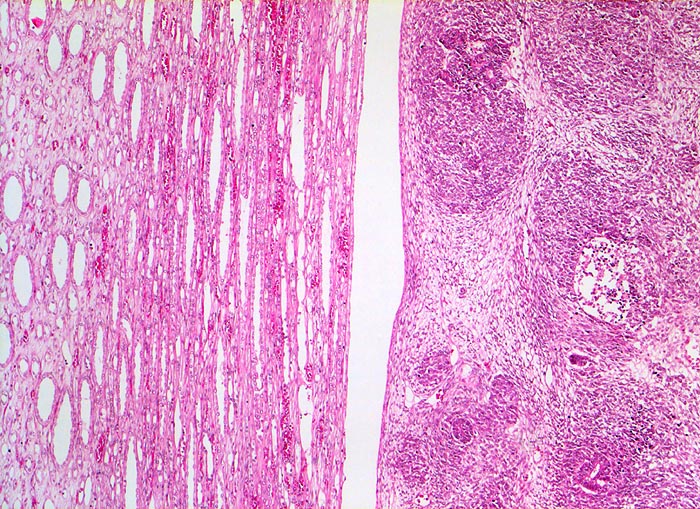

PathoPic ID 5179 - Wilms-Tumor

Wilms-Tumor

maligner Tumor

Niere

Paidopathologie

Das Nierenmark (links) wird durch den expansiv wachsenden scharf begrenzten Tumor (rechts) lediglich

komprimiert, nicht aber infiltriert.

Graubrauner scharf begrenzter weicher Tumor mit fokalen Nekrosen und Einblutungen.

Palpabler Tumor im linken Hemiabdomen. Makrohämaturieepisode.

Histologie

50

1

männlich